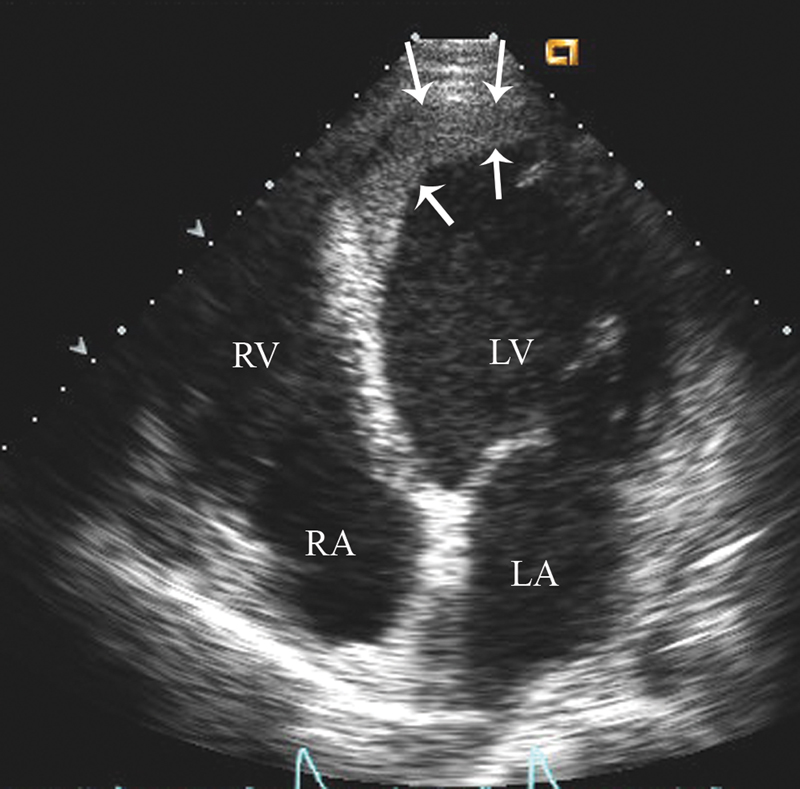

فحوصات تشخيصية لبعض امراض القلب والشرايين التاجية